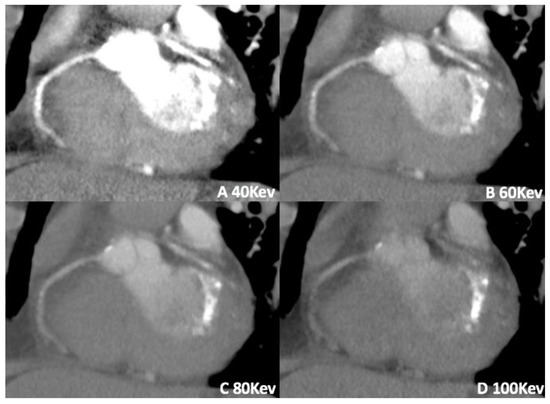

3.1. Virtual Monoenergetic Imaging (VMI)